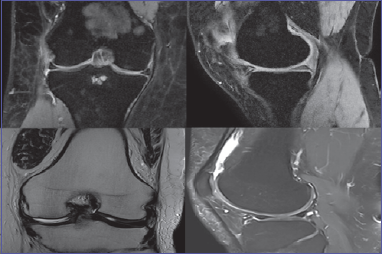

All patients underwent an MRI before the surgery to have a further estimate of the arthritic picture and of any meniscal lesions or any chondropathies using the Modified Outerbridge classification (Fig. 1). All those who underwent other articular injected therapies in the previous 3 months or knee surgery treatments in the previous 6 months were excluded. It was decided to evaluate the effectiveness of the treatment in terms of functionality using the Womac Score (The Western Ontario and McMaster Universities Osteoarthritis Index) which consists in 3 subscores used to classifying pain, stiffness and functionality, with a range from 0 to 56. A decreasing trend indicates improvement in functionality, pain, and stiffness reduction. The Womac score was proposed to patients before surgery and at the time of the follow-up assessment six months and one year after surgery.

Figure 1.Preoperative MRI.